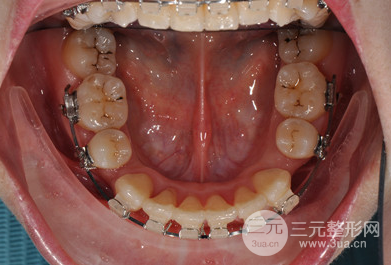

在做牙齿正畸这段时间里,一直都坚持饮食清淡和清洁工作,不能过度咀嚼,所以在着两年多的坚持下还是有很明X的改良的。

矫正期间没个一段时间就要回医院做复查和更换牙套,好在医生的技术比较好,牙齿矫正比较争气,现在想过很满意,不仅没有凸嘴,牙齿也很整齐,现在已经取了牙套之后可以随意吃吃喝喝了,这两天没有白坚持。